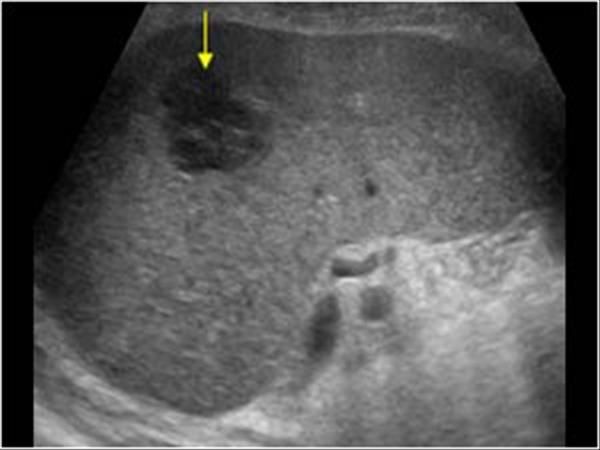

Рис. 1. Метастатическое поражение головного мозга при лимфосаркоме.